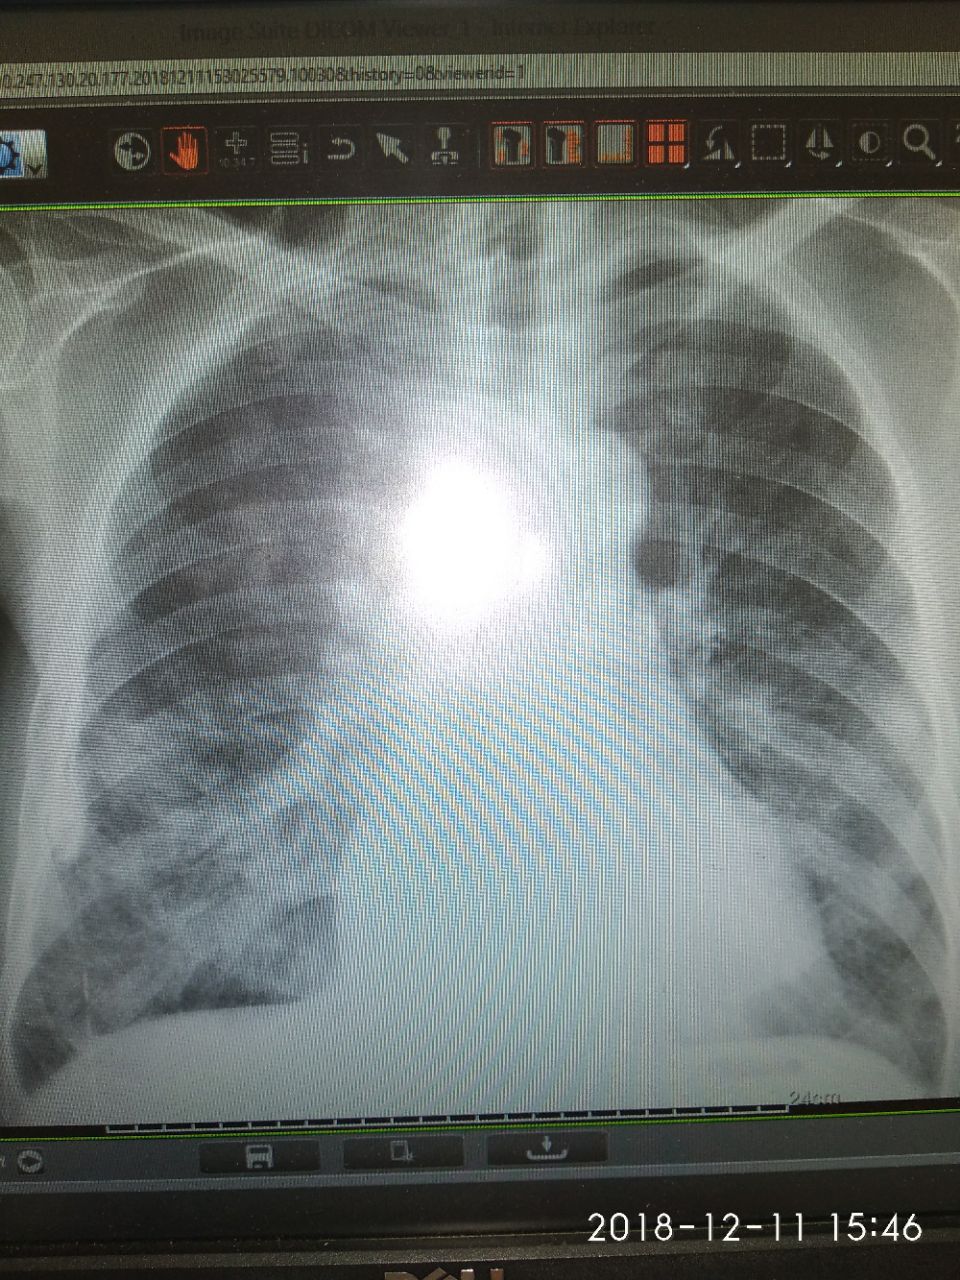

Больной 1940г.р ИБС. Стенокардия ФК2.

06.12.2018 поставил прав н/д бронхопневмония. Снимок сравнивал изм нету.

Фиброз? Бокового нет?

Мне интересуют это

Спайки плевральные паракостально?

Остаточное изменение правостороннего осумкованного плеврита?

Остаточное изменение правостороннего осумкованного плеврита?

Ну.. просто плеврита